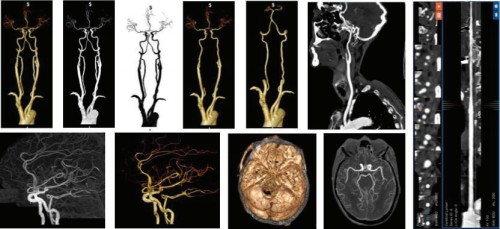

头颈CTA

头颈cta图像